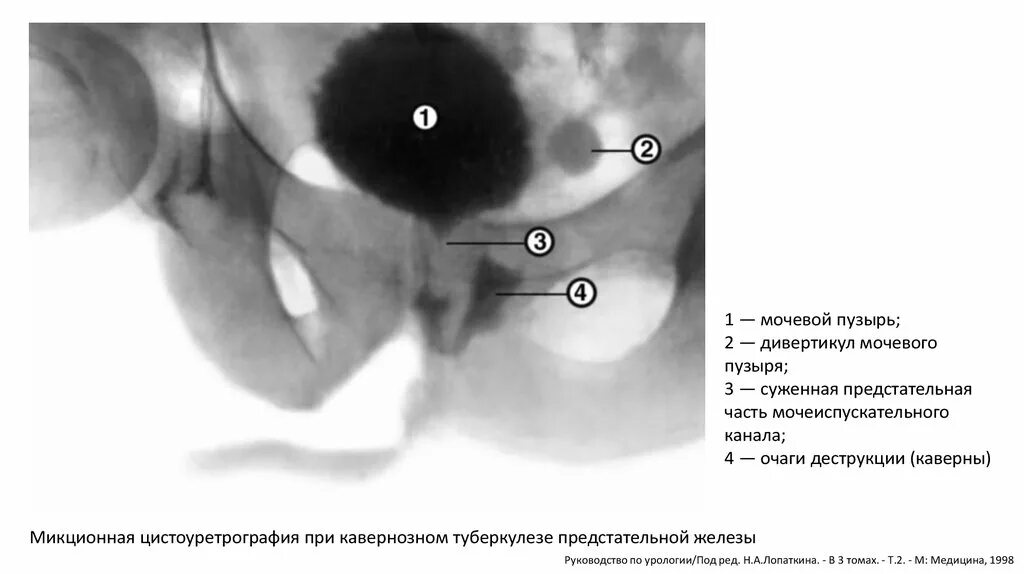

Дивертикул мочевого пузыря что это такое